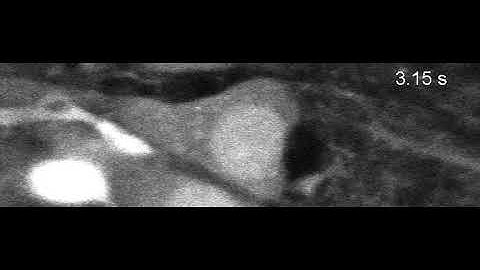

Calcium Imaging of Neurons in Mouse Primary Visual Cortex